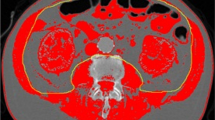

CT scans were imported from the local radiology system and assessed for quality. First, the third lumbar vertebra (L3) was identified on abdomen CT scans. This landmark was chosen because of its established correlation with whole-body muscle mass [17–19]. The L3 slice provides information on a number of muscles: the erector spinae-, quadratus lumborum-, psoas-, transversus abdominis-, interior- and exterior oblique-, and rectus abdominis muscles. The L3 slice was isolated and stored for later analysis.

CT scan analysis was performed by using Slice-O-matic version 4.3 and 5.0 (TomoVision, Montreal, QC, Canada) by trained personnel. Muscle tissue was identified by using boundaries in Hounsfield Units set to -29 to +150 [18]. The software computed a muscle surface area in cm2 by multiplying the pixel area by the amount of pixels identified as muscle.